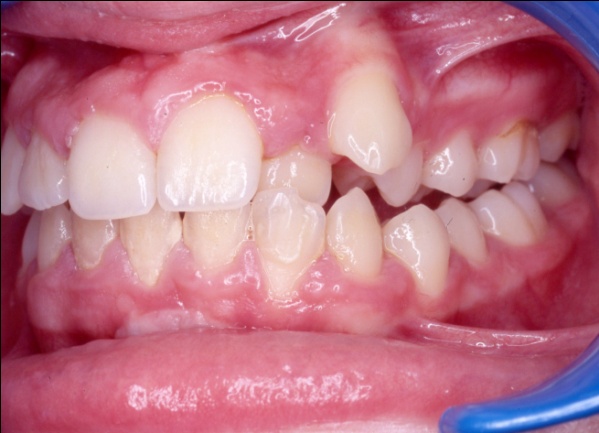

Ce cas illustre parfaitement que l’orthodontie ne peut pas se résumer à un simple alignement des dents. Ici, l’exclusion de la canine supérieure gauche (23) pouvait faire croire à un manque de place dû à un excès de volume dentaire. En réalité, un diagnostic précis a révélé deux causes : une endomaxillie (palais trop étroit) et une avancée anormale de l’hémiarcade gauche, qui empiétait sur l’espace de la canine. Le traitement a consisté à élargir le maxillaire par disjonction, puis à réaligner les dents sans extraction, en restaurant l’harmonie occlusale.

1 - Arcades avant/après

Le traitement a été conservateur, sans extraction, grâce à une thérapeutique de gain d’espace adaptée. L’arcade a retrouvé sa largeur, son équilibre et son esthétique, par la restitution d’une architecture osseuse et dentaire cohérente. L’occlusion est désormais fonctionnelle, stable et conforme aux rapports naturels entre les deux arcades.